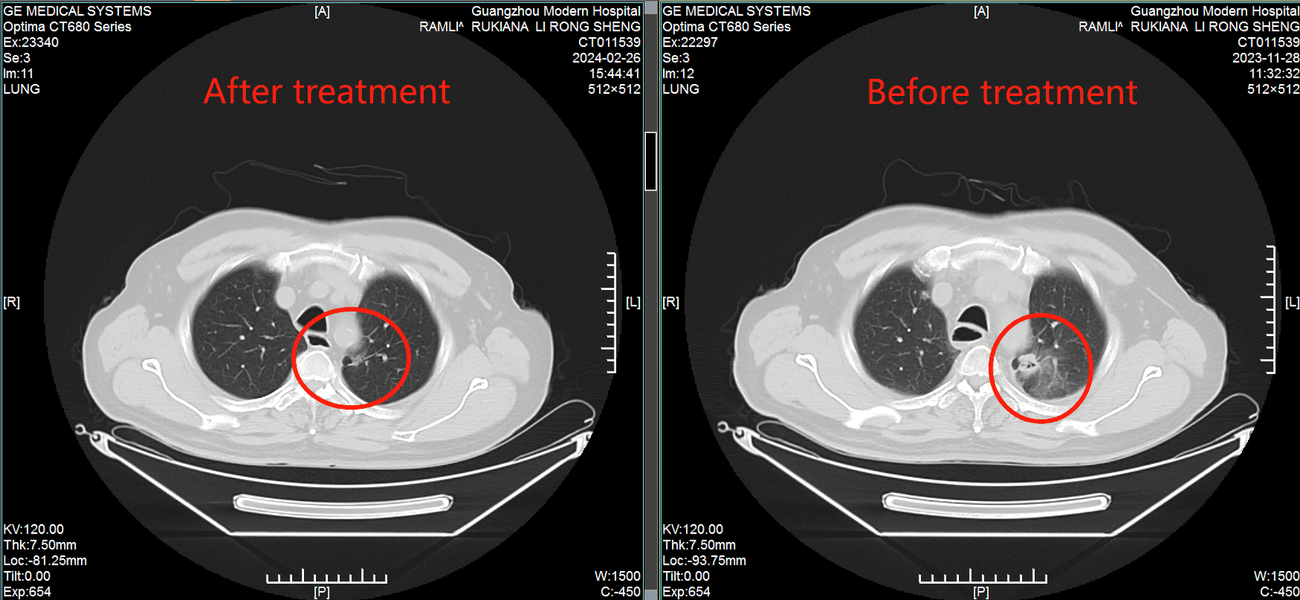

История победы: тайский генерал против рака легких с метастазами

70-летний Сурьякул На Аюдхая Ювануд нашел спасение в малоинвазивных технологиях после рецидива рака

В 2021 году у генерала Ювануда из Таиланда диагностировали рак легких. Несмотря на операцию и курсы химиотерапии, болезнь вернулась с метастазами. Возраст и гипертония сделали дальнейшее традиционное лечение невозможным. К 2023 году состояние ухудшилось: одышка, слабость, необходимость в инвалидном кресле. Семья не сдалась. По рекомендации друга, победившего рак гортани в той же клинике 10 лет назад, генерал обратился в Modern Cancer Hospital Guangzhou.

Прорыв: комплекс малоинвазивных методов

Мультидисциплинарная команда клиники разработала персонализированный план: 1. Интервенционная терапия - доставка химиопрепаратов непосредственно в опухоль через артерии. 2. Имплантация радиоактивных частиц - точечное уничтожение метастазов. 3. Иммунотерапия - активация собственных защитных сил организма. Результат через 2 курса лечения: • Опухоль уменьшилась на 60%. • Исчезли одышка и необходимость в инвалидном кресле. • Риск синдрома верхней полой вены устранен. «Интервенционная терапия бьет точно в цель, не затрагивая здоровые ткани. Это главное преимущество», - отмечает супруга генерала.

Жизнь после лечения Сегодня генерал Ювануд: • Самостоятельно передвигается и путешествует. • Вернулся к активной жизни без болей и одышки. • Проходит поддерживающую терапию с уверенностью в будущем. Его супруга добавляет: «Врачи не только продлили ему жизнь - они вернули ему её качество».